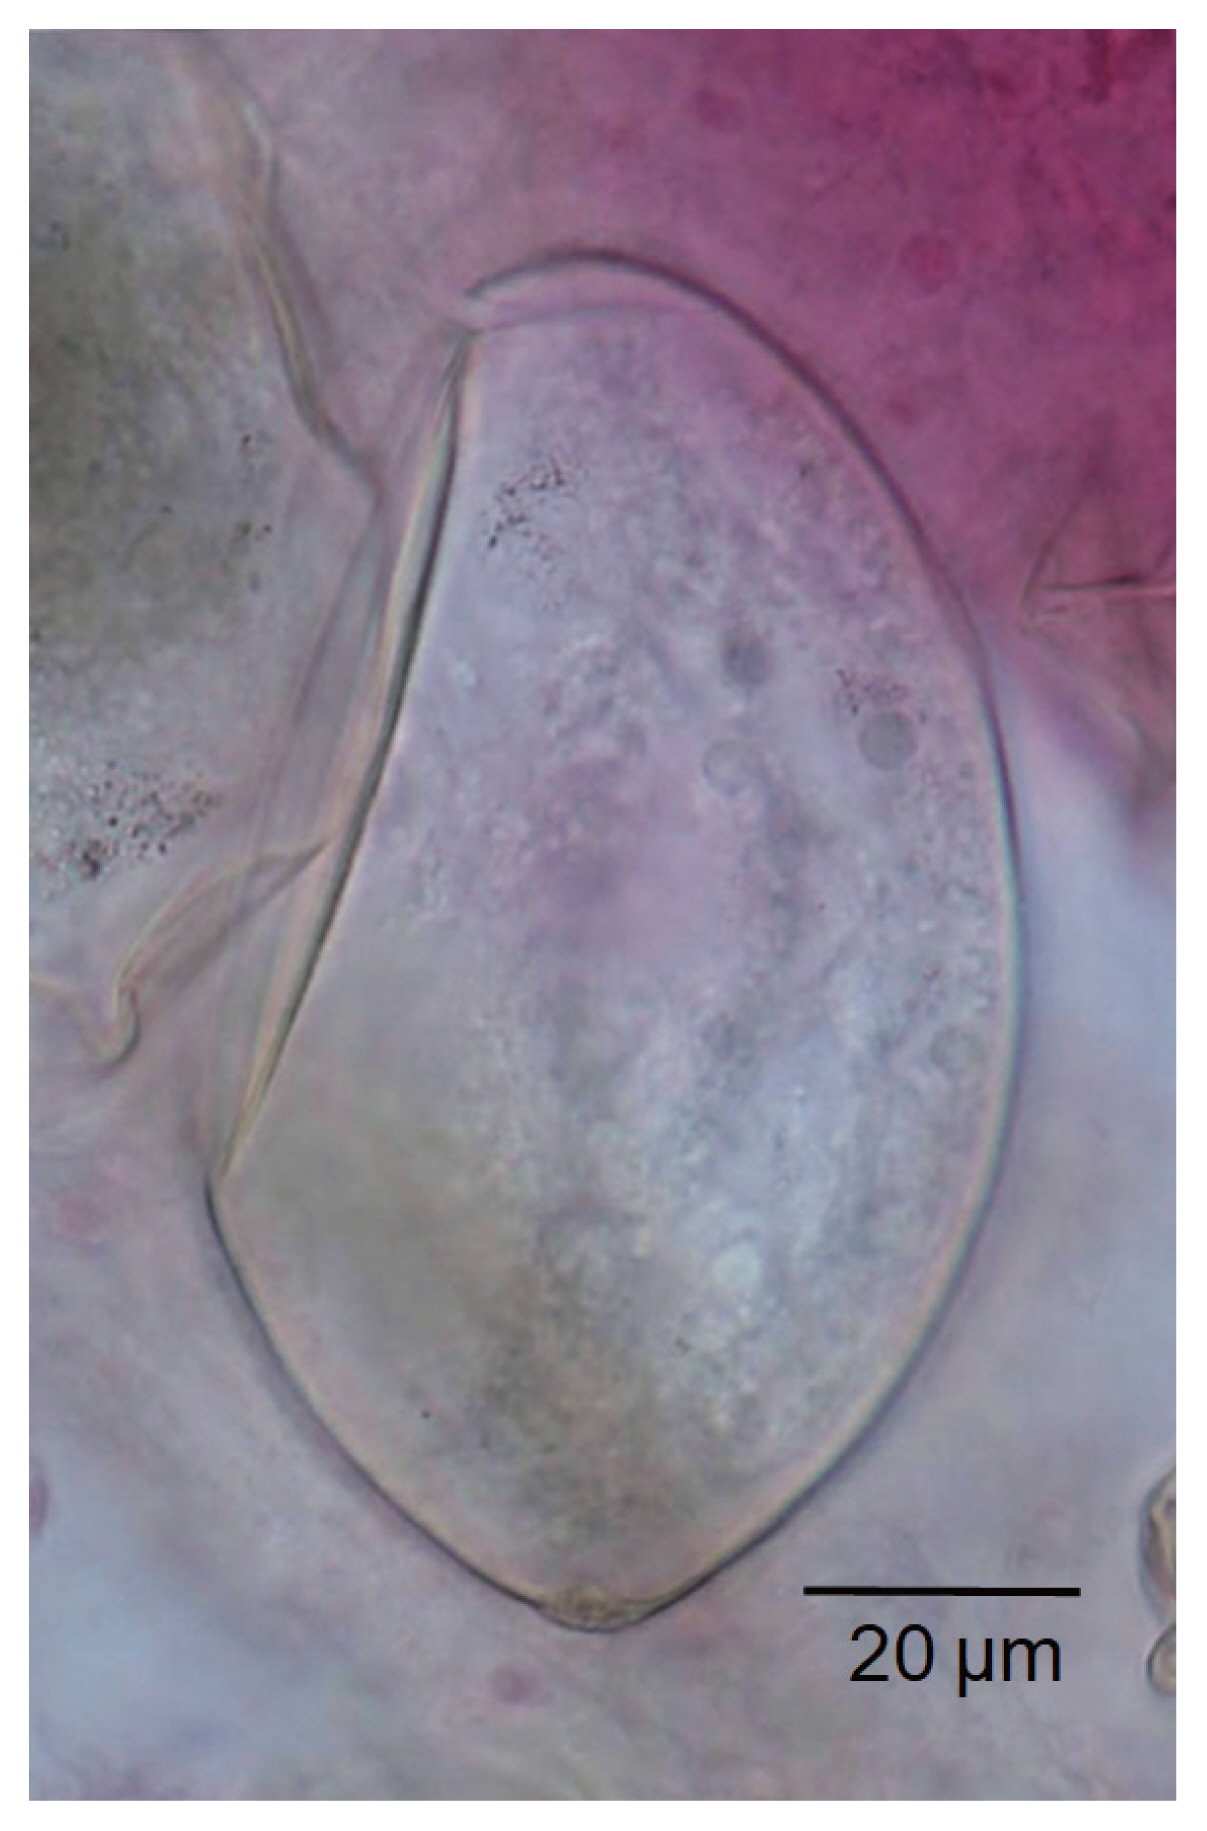

Echinostoma aegyptica (Trematoda: Echinostomatidae) Infection in Five Riparian People in Savannakhet Province, Lao PDR

The Korean Journal of Parasitology 2020;58(1):67-72.